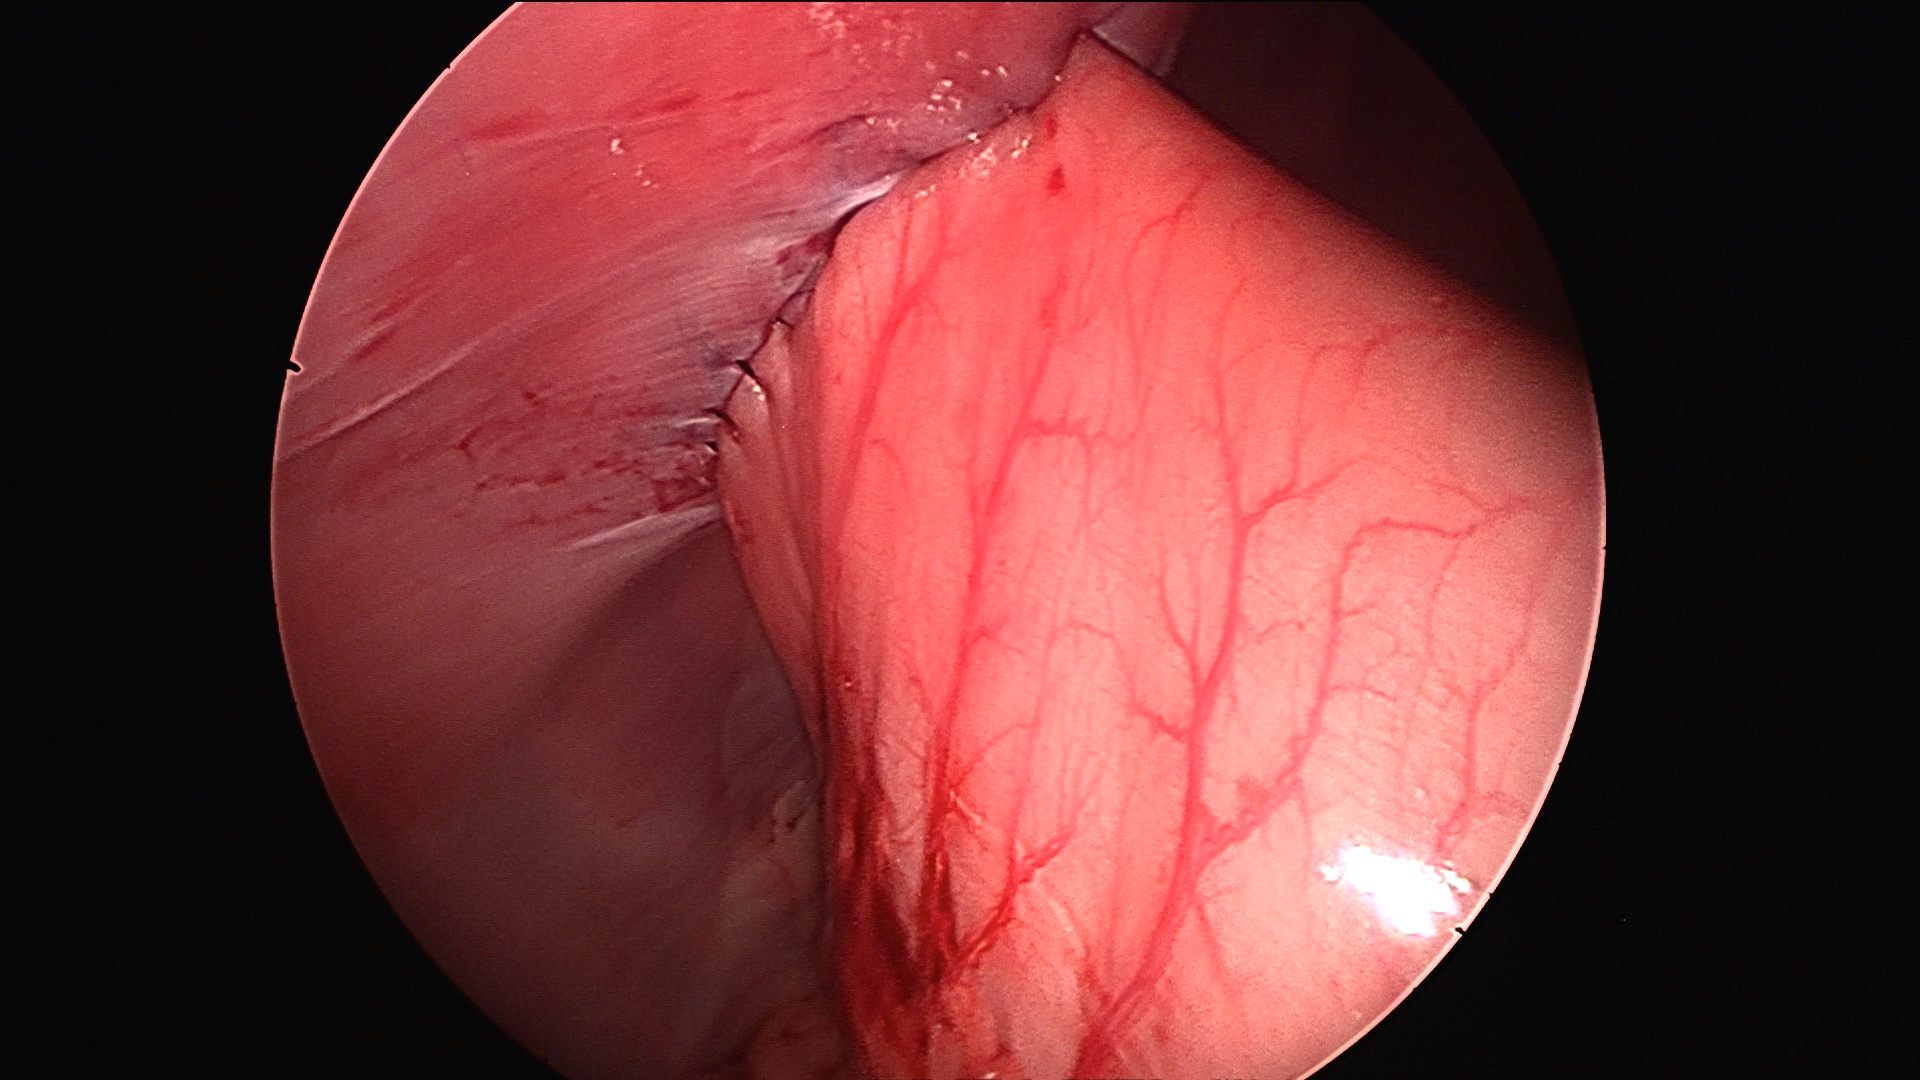

Appearance of the stomach being grasped by forceps to be sutured to the abdominal wall

Final appearance of the stomach sutured to the body wall to prevent twisting just prior to the gas being removed from the abdomen (to remove the tension)